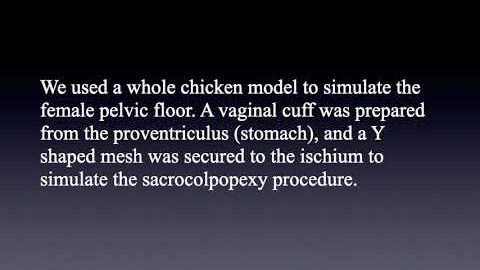

#255 A cost-effective model for training in Robot-Assisted Sacrocolpopexy- Dr. Yair Daykan